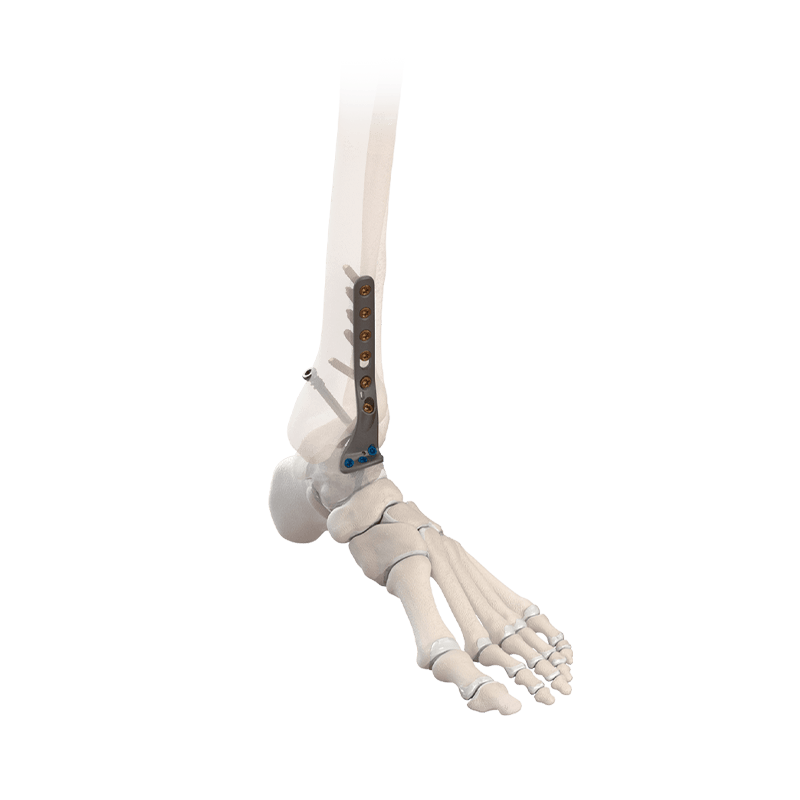

Fixation Devices - Plating Systems

CoLink® Afx Ankle Fracture Plating System

Five plate families that address traumatic fractures and osteotomies of the ankle

CoLink® NeoFuse Ankle Fusion Plating System

For anterior fixation of ankle arthrodesis and fractures